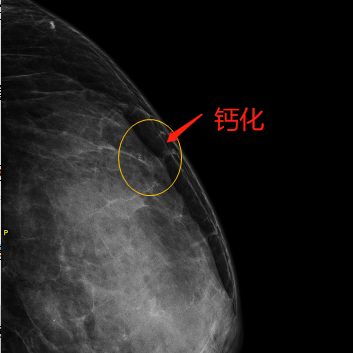

张女士五十出头,来医院常规体检,乳腺彩超没有发现特殊异常,但是乳腺钼靶提示左乳有一个“绿豆”大小的团簇状钙化。医生建议张女士住院,把异常钙化切除送检,术后病理提示为乳腺导管原位癌,癌组织直径只有2.5mm。

张女士钼靶所见异常钙化

它的特点是可以检测出医生触摸不到的乳腺肿块,特别是对于大乳房和脂肪型乳房,其诊断性可高达95%,对于以少许微小钙化为唯一表现的T0期乳腺癌(临床门诊阴性),也只有凭借软X线检查才能被早期发现和诊断。

灵敏度高。可以发现≤1.0cm的乳腺癌微小病灶和部分隐匿性病灶,敏感度85~90%,而且降低了放射剂量。乳腺钼靶对于彩超和核磁无法鉴别的钙化病变可以进行准确辨别。钼靶+彩超是乳腺筛查的金标准。

特别提醒

真正早期乳腺癌多数临床上是不能触及肿块的,而乳腺实质内的钙化,则是早期乳腺癌最常见甚至是唯一的征象。临床证实,乳腺钼靶X线摄影术的应用使早期乳腺癌的检出率明显增高。